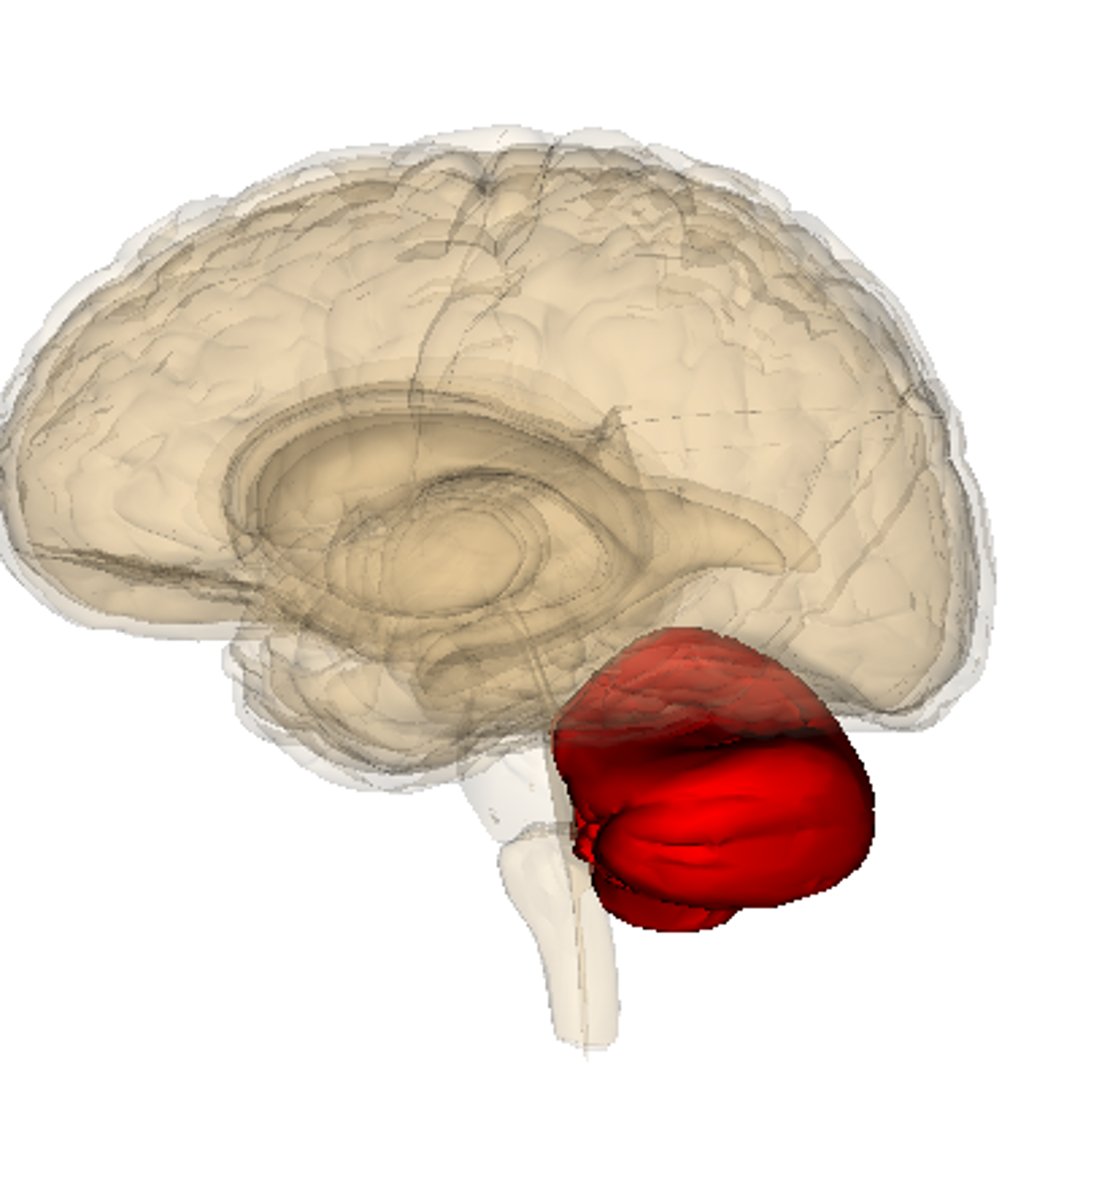

Cerebellum

rear of the brain stem - processing sensory input, coordinating movement and balance, nonverbal learning and memory